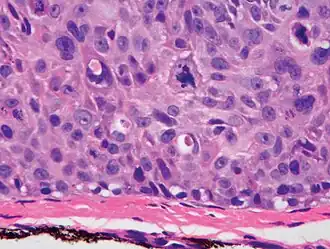

Invasive disease

In invasive SCC, tumor cells infiltrate through the basement membrane. The infiltrate can be somewhat difficult to detect in the early stages of invasion: however, additional indicators such as full thickness epidermal atypia and the involvement of hair follicles can be used to facilitate the diagnosis. Later stages of invasion are characterized by the formation of nests of atypical tumor cells in the dermis, often with a corresponding inflammatory infiltrate.[33]

Superficially invasive squamous cell carcinoma (SCCSI). These lesions often do not show the marked pleomorphism and atypical nuclei of SCC in situ, but demonstrate early keratinocyte invasion of the dermis.[33] -

High magnification demonstrates the pleomorphism of the invading keratinocytes.[33] -

Invasive nests with characteristic large celled centers. Ulceration (at left) is common in invasive SCC.